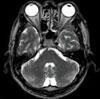

MRI検査

MRI(Magnetic ResonanceImaging)は、大きな磁石による強い磁場とFMラジオに使われているような電波を使って、体の断層画像を得る検査です。CTとの大きな違いは、X線を使わない画像診断です。

令和6年4月に新しく3T装置を導入し、より詳細な検査を行うことが出来るようになりました。また、開口径のより広いワイドボアを採用しています。身体の大きな方、狭いところが苦手な方にも対応することが可能です。